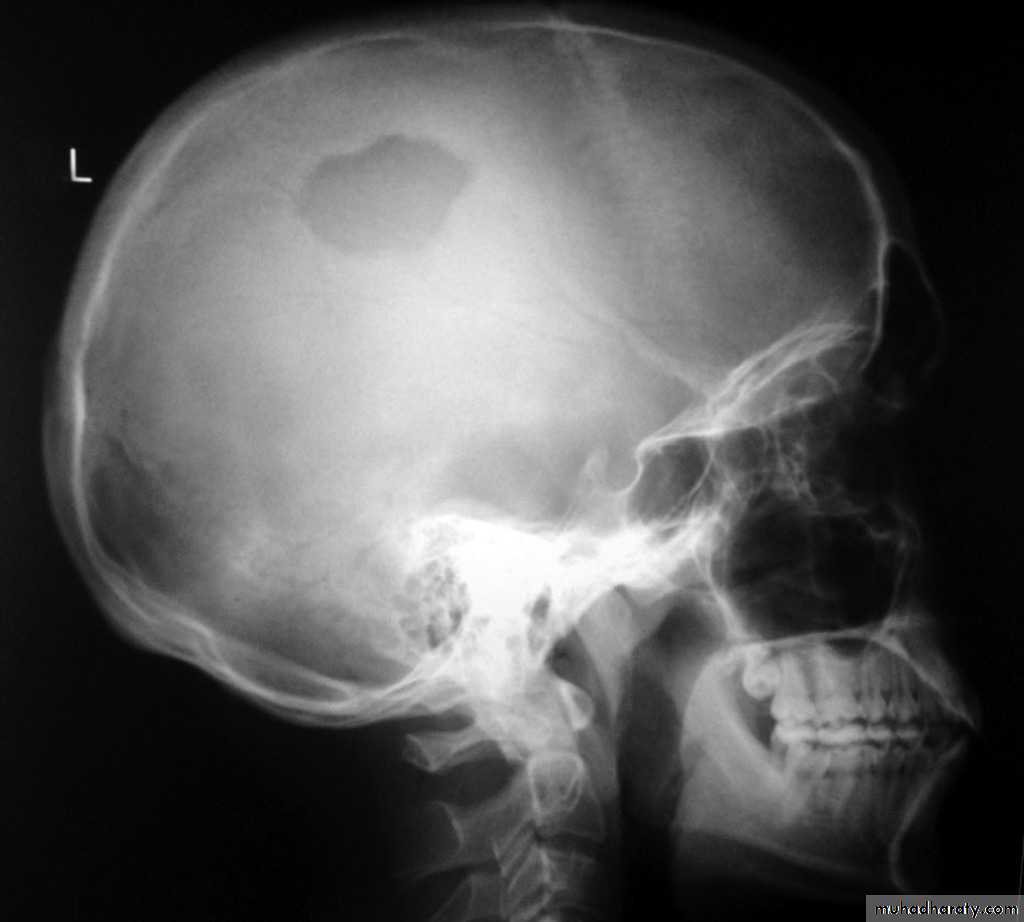

Skull X-rayBony configuration and shape

Bone densityAny Lytic lesion

Any fracture

Any calcification

Diploë, pituitary fossa, paranasal sinuses, orbits

The sutures

The normal pituitary fossa as shown in a lateral skull film can vary considerably in size. Normal figures are (length of 11-16 mm and a depth of 8-12 mm)